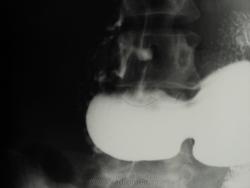

на ФГДС в 2000 г. описывают "целующиеся" язвы луковицы ДПК на передней и задней стенках до 1 см в диаметре.

По всей видимости, процесс "целования" закончился, на мой взгляд в растоящее время будцовая деформация по "варианту трилистика".